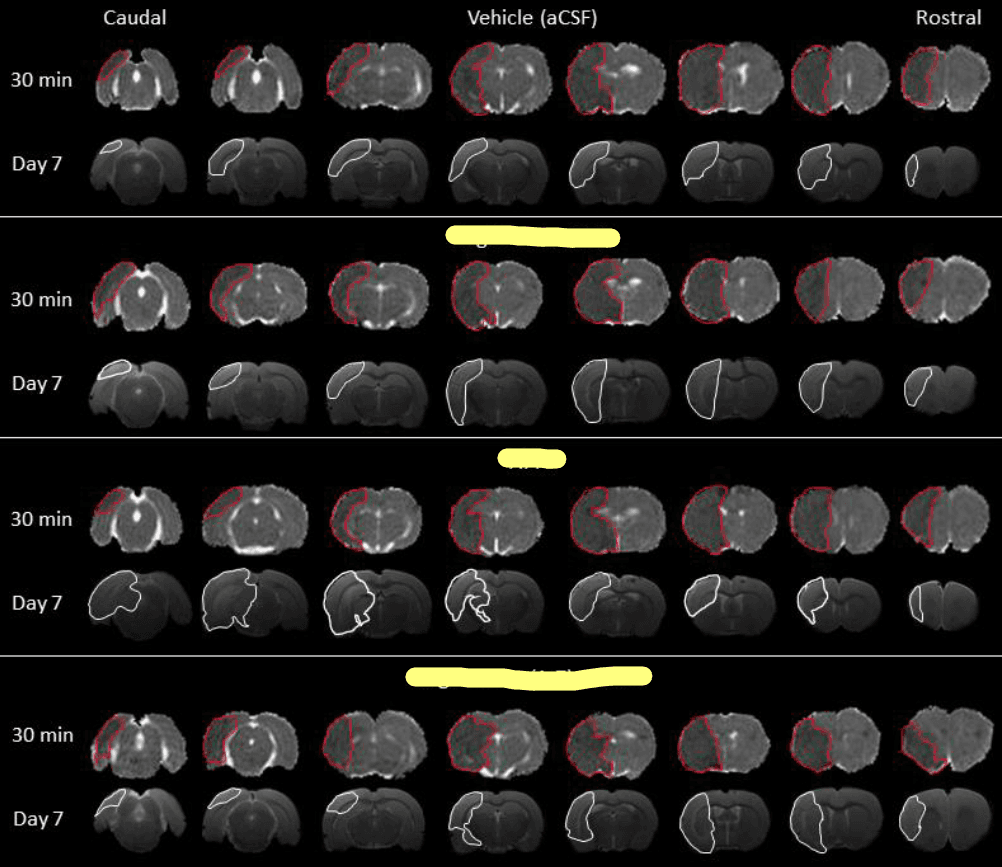

Today, the lab came alive with the hum of computers as I delved deep into the intricate world of image analysis. The task at hand was to sift through numerous MRI scans, collected during a trailblazing experiment designed to explore potential new treatments for stroke. I've attached an example of these images below to provide a clearer idea of the kind of analysis undertaken. Although a considerable amount of mathematics is involved, the whole process is semi-automated thanks to specialised software designed for this type of analysis. The process, albeit lengthy, offers an exciting journey through the maze of data. In fact, I anticipate spending several more days to complete the entire data set's analysis. Despite the task's enormity, the thrill of familiarising myself with the image analysis software has been a rewarding experience.

Today's approach to image analysis begins with identifying the initial infarct occurring 30 minutes post-stroke, defined as the hypo-intense area on quantitative apparent diffusion coefficient (ADC) maps. These maps are constructed from diffusion-weighted MRI images. To calculate the initial infarct volume for each brain, we multiplied this area on each slice by the slice thickness and then summed up the values from all eight slices.

Seven days after the stroke, the final infarct was defined by manually delineating the hyperintense area on T2-weighted MRI images. We then multiplied the infarct area from each slice by the slice thickness and summed these to calculate the lesion volume for each brain.

A Diffusion Weighted Imaging (DWI) scan was obtained 30 minutes post-stroke to facilitate quantitative ADC map production and assessment of ischaemic tissue. The treatment was administered intracerebroventricularly via an osmotic pump inserted subcutaneously at the back of the neck, connected to a cannula inserted into the right lateral ventricle via a burr hole drilled in the contralateral skull. Post treatment, recovery was allowed for seven days, after which T2-weighted MRI images were obtained to evaluate the final infarct volume.